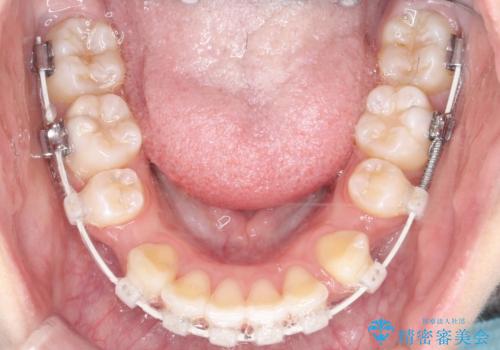

- ハーフリンガル

目立たない装置が希望とのことでハーフリンガルで治療をすることとしました。

当院では裏側矯正という方法も提供しています。裏側矯正は、装置を歯の裏側に取り付けるため、外側からは目立ちにくくなります。この治療法は、見た目に気を使いたい方に特におすすめです。